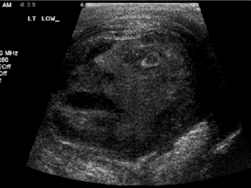

Urólogos sorprendidos con imagen de rostro en un tumor

Un rostro apareció cuando urólogos canadienses realizaban un examen de ulrasonido a un tumor grande de testículo a un paciente de 45 años.

Tan extrañados se sintieron los doctores G. Gregory Roberts y Naji J. Touma, de la Queen’s University en Ontario, que publicaron la curiosidad en el diario de la Sociedad Internacional de Urología.

“Los residentes y el personal estaban sorprendidos al notar la forma de un rostro humano mirando hacia arriba”, señalaron en el número de setiembre de esa revista científica.

Finalmente, el testículo afectado por el tumor fue extirpado.